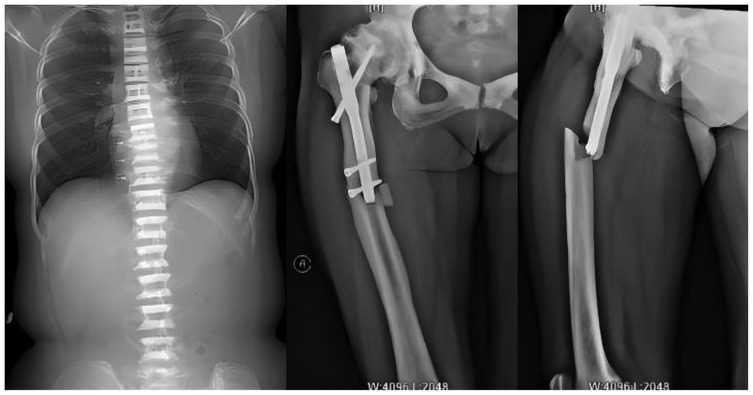

A 59-year-old woman presented to our emergency department on 5 October 2021 with right thigh pain and limited mobility following an accidental fall while walking. On admission, physical examination revealed significant swelling of the right thigh, visible subcutaneous bruising, marked tenderness on palpation, positive percussion pain, negative pelvic separation compression test, normal range of motion at the knee and ankle joints, and normal peripheral circulation and sensation in the affected limb. To confirm the diagnosis, the patient underwent right femur anteroposterior and lateral x-ray examinations (Figure 1), which showed: Continuity of the cortical bone was interrupted around the internal fixation of the right femoral shaft, and the bone density was abnormally increased, with rough and blurred trabeculae, thickened cortical bone, and narrowed medullary cavity; Full-length anteroposterior x-ray examination of the spine (Figure 1) shows that the density of the upper and lower edges of the vertebral body is increased, and the middle density is lower, showing a “sandwich” change, which is a typical imaging manifestation of osteopetrosis. The clinical diagnosis was: (1) fracture around the internal fixation of the right femur; (2) osteopetrosis; (3) right hip arthritis. Upon further inquiry into the patient's medical history, he reported that he had suffered a right femoral intertrochanteric fracture due to a car accident in 2014, and was also found to have osteopetrosis and hip joint necrosis. At that time, the doctor recommended joint replacement surgery to treat both the fracture and joint necrosis, but the patient refused the surgery because he was young at the time. He then underwent intramedullary nail internal fixation to treat the fracture, which healed well, and he resumed his normal life. The patient has no history of severe internal medical conditions. The patient was referred to our orthopaedic ward for further treatment and is scheduled to undergo fracture surgery.

Figure 1. Full-length anteroposterior x-ray film of spine showed that the bone density of upper and lower parts of vertebral body increased, while the density of middle part was lower; preoperative anteroposterior and lateral x-ray images of the right femur show fractures around the internal fixation of the right femur, with signs of hip osteoarthritis and abnormally high bone density.